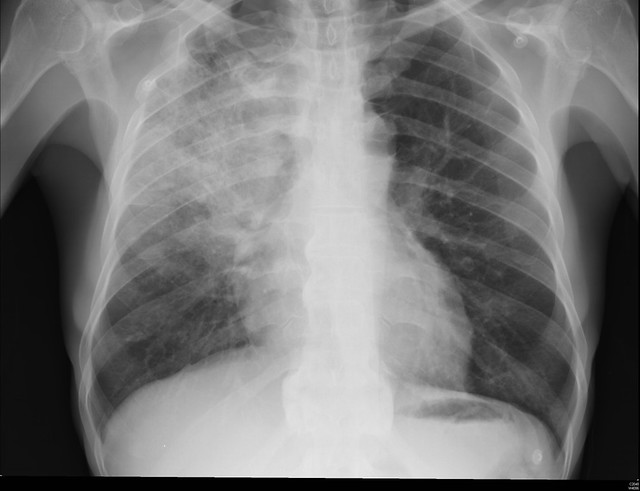

With that context in mind, the researchers studied patients treated in the hospital for pneumonia. The study involved the Michigan Hospital Medicine Safety Consortium, a network about 50% of Michigan’s nonfederal hospitals. [1] Patients all had a diagnosis of community or hospital-acquired pneumonia, evidence of pneumonia on examination and at least a 4-day hospital course of antibiotics. [2] Excessive days were defined as any course of treatment longer than national guidelines, and because of the vagaries in how this data is computed, you were compliant if the prescription was within a day of the recommendation. Outcomes came from medical records as well as 30-day follow up telephone conversations with patients. The study included 87% of eligible patients, roughly 6500 with a median age of 70, and about 75% had a community-acquired pneumonia. [3]

[3] The distinction is made between community and hospital-acquired pneumonia because the suspected microbe differs.